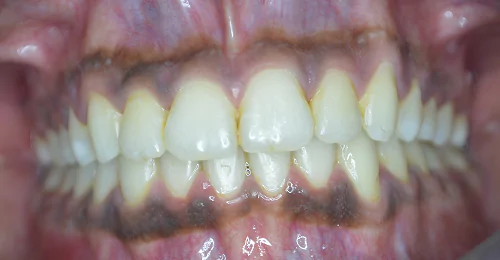

Orthodontic Case – II

(Case Done by Dr. Sonali Deshmukh M.D.S. / Orthodontist )

Correction Of Protruded

Small Lower Jaw

A child with protruded teeth and a small lower jaw at a young age can be treated by Myofunctional appliances which help in the growth of the jaw.

Pre Treatment

After Myofunctional appliances therapy for jaw growth accompanied by braces treatment for correction of protruded teeth.